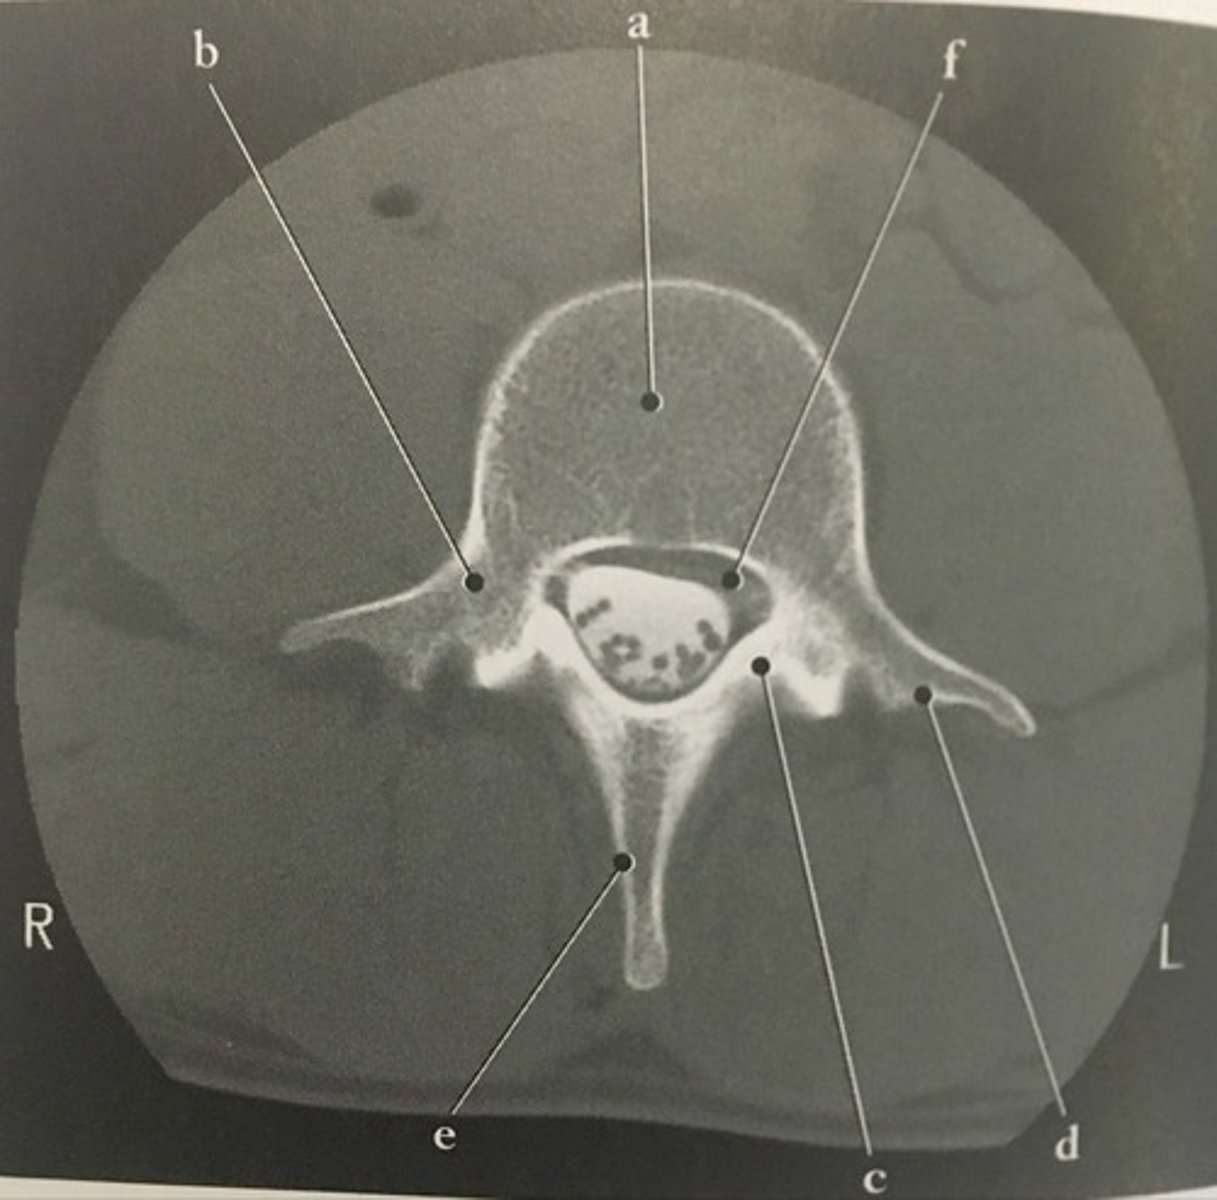

Body

Identify structure A on this axial CT slice of the lumbar vertebra.

<p>Identify structure A on this axial CT slice of the lumbar vertebra.</p>

Pedicle

Identify structure B on this axial CT slice of the lumbar vertebra.

<p>Identify structure B on this axial CT slice of the lumbar vertebra.</p>

Lamina

Identify structure C on this axial CT slice of the lumbar vertebra.

<p>Identify structure C on this axial CT slice of the lumbar vertebra.</p>

Transverse process

Identify structure D on this axial CT slice of the lumbar vertebra.

<p>Identify structure D on this axial CT slice of the lumbar vertebra.</p>

Posterior spinous process

Identify structure E on this axial CT slice of the lumbar vertebra.

<p>Identify structure E on this axial CT slice of the lumbar vertebra.</p>

Vertebral foramen

Identify structure F on this axial CT slice of the lumbar vertebra.

<p>Identify structure F on this axial CT slice of the lumbar vertebra.</p>